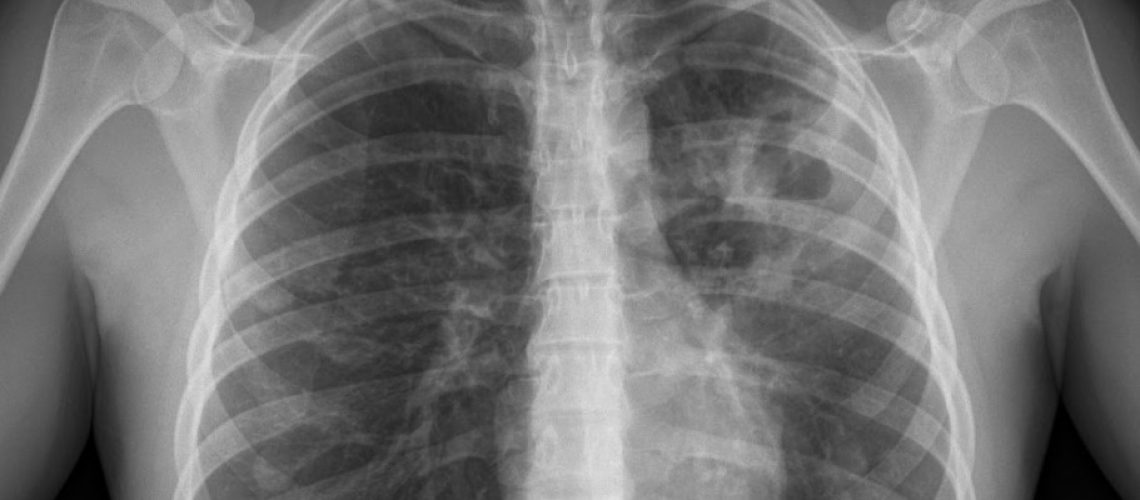

La tuberculosis es probablemente la enfermedad infecciosa mas antigua de la humanidad, además de la más prevalente. La antigüedad de esta infección se ha estimado en mas de 3 milllones de años. La edad media de presentación es de 35-44 años y predomina en varones. Esta producida por un bacteria denominada Mycobacterium tuberculosis y el reservorio del bacilo son los individuos y animales infectados. Afecta preferentemente a los pulmones aunque también puede afectar a otros organos. Los síntomas son inespecíficos y muy variables. Las manifestaciones generales clásicas consisten en un cuadro subagudo o crónico caracterizado por adelgazamiento, cansancio, perdida de apetito y febrícula de predominio vespertino con sudoración nocturna. El síntomas respiratorio mas frecuente es la tos y puede aparecer expectoración con sangre o dificultad para respirar en fases mas avanzadas de la enfermedad. Es fundamental el diagnóstico precoz para controlar la enfermedad ya que la contagiosidad disminuye desde que se inicia el tratamiento.